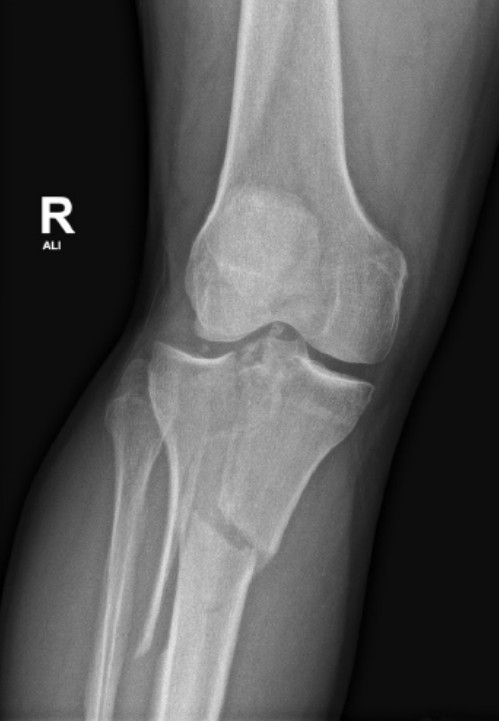

High-energy tibial plateau fracture

A 28-year-old man presents with an isolated right leg injury after a motorbike accident. An X-ray is provided.